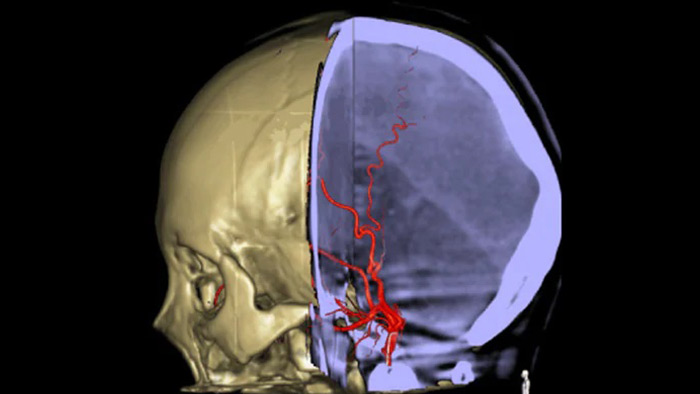

SmartCT Vaso IV

Verificar a localização e a dimensão de um coágulo

O SmartCT Vaso permite a visualização para além do coágulo com imagens peri-procedimento dos aspetos do vaso distal nos acidentes vasculares isquémicos. O SmartCT Vaso é uma técnica de aquisição baseada no exame de TC de feixe cónico e numa injeção de contraste intra-arterial. Permite a visualização para além do coágulo com as imagens peri-procedimento dos aspetos do vaso distal nos acidentes vasculares isquémicos. Através do enchimento retrógrado, as estruturas do vaso antes e depois do coágulo ficam visíveis. O SmartCT Vaso 3D Roadmap pode ser utilizado para visualizar dispositivos de recuperação do coágulo.

As referências anatómicas suportam uma navegação 3D precisa

Mapa SmartCT, navegação 3D precisa

O SmartCT Roadmap fornece referências anatómicas para apoiar a navegação precisa do fio-guia, do cateter e do dispositivo até ao coágulo.